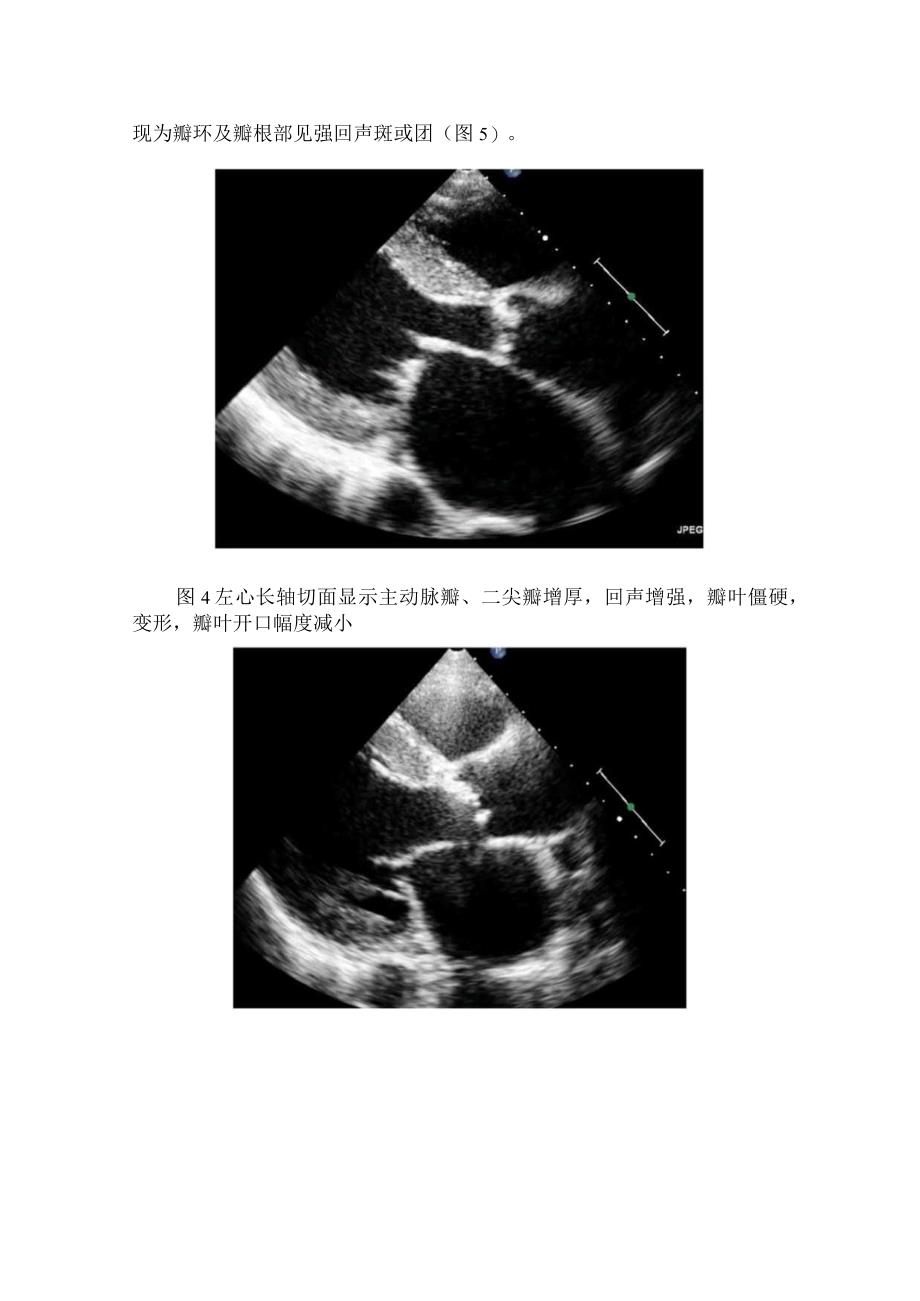

2、。这时候左心室和主动脉之间存在压差,导致左心室排血受阻,为了维持正常心输出量,左心室需增加收缩力,造成心肌向心性肥厚,升主动脉可出现狭窄后扩张。对于主动脉瓣狭窄的超声检查,我们主要采用的切面为左心室长轴切面和主动脉短轴切面,以此观察主动脉瓣形态、瓣叶数目,估测瓣口面积;其次通过心尖五腔或三腔心两个切面,定量检测主动脉口流速、跨瓣压差。后天性主动脉瓣狭窄的超声诊断要点风湿性心瓣膜病所致主狭主要表现为主动脉瓣增厚,回声增强,瓣叶僵硬,变形,瓣叶开口幅度减小,二尖瓣也有相似表现(图4);退行性变表现为瓣环及瓣根部见强回声斑或团(图5)。图4左心长轴切面显示主动脉瓣、二尖瓣增厚,回声增强,瓣叶僵硬,变

3、形,瓣叶开口幅度减小图5退行性病变所致主动脉瓣增厚,回声增强,瓣叶活动受限,二尖瓣活动尚可彩色多普勒超声显示收缩期主动脉瓣口血流加速,为五彩镶嵌的高速射流(图6),狭窄越重,流速越高。图6心尖三腔心切面显示主动脉瓣叶增厚,回声增强,收缩期主动脉瓣口为五彩高速射流束连续多普勒通过心尖五腔或三腔心这两个切面,估测主动脉瓣的流速及平均跨瓣压差:轻度狭窄主动脉峰值流速为2.62.9ms,平均压差V20mmHg;中度狭窄峰值流速为3.04.Oms,平均压差为2040mmHg;重度狭窄峰值流速大于40ms,平均压差40mmHg0图7心尖五腔心切面显示峰值流速大于4ms主动脉瓣狭窄超声上主要表现为主动脉瓣增厚,回声增强,活动受限,瓣口开放面积减小。主动脉瓣收缩期出现高速血流信号,并可探及瓣口两侧存在压差,长期左心室可出现向心性肥厚,升主动脉可出现狭窄后扩张。2017年AS超声评估指南主动脉前狭窄严重程度分级标准(ASE2017)主动脉硬化轻度中度*度峰使漉速(ms)4.0平均低差(mmHg)*40主动脉门面取(Cm)*1.51.0-1.50.850.60-0.850.500.25-0.500.25